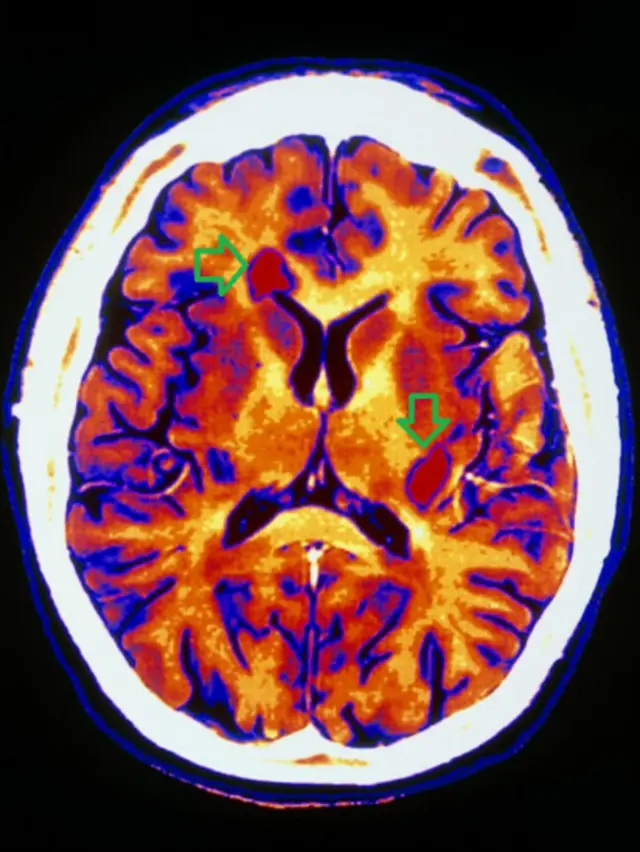

اما پس از درمان با این روش، در امآرآی هیچ ضایعه جدیدی دیده نشد، سرعت تحلیل مغز به قدری کاهش یافت که به فرد سالم نزدیک شد، عود بیماری مشاهده نشد و میزان ناتوانی و معلولیت بیماران کاهش یافت.